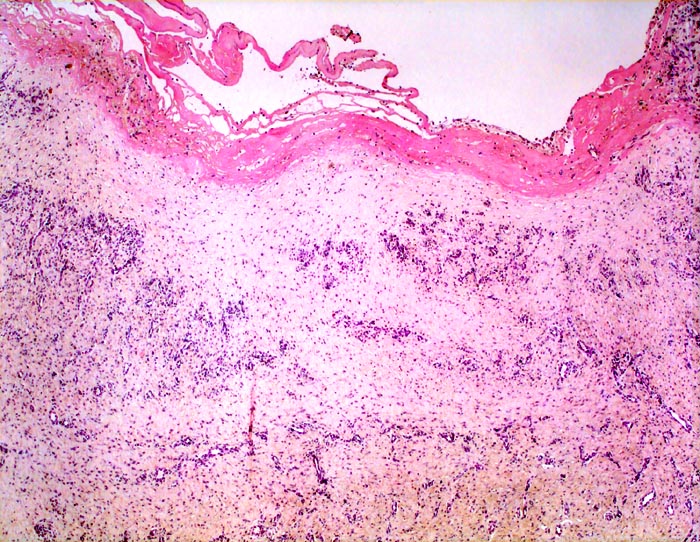

chronische Bursitis

Bursa praepatellaris

Bursawand fibrös (= narbig) verdickt. Der Bursainnenseite aufgelagerter Fibrinpelz. Bursawand mit Organisationsgewebe mit vielen bäumchenartig gewucherten kapillären Gefässen, dazwischen zellarmes Narbengewebe.

Der anatomische Aufbau der Bursa entspricht dem einer Gelenkkapsel oder Sehnenscheide; von innen nach aussen:

- Ein- bis zweischichtige Zellschicht aus Synoviozyten

- Lockeres, zell- und gefässreiches Stratum synoviale

- Straffes Stratum fibrosum